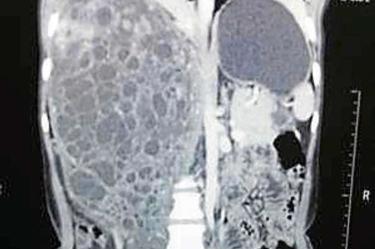

Una tomografía computarizada reveló que el tumor había cubierto casi por completo al riñón derecho, comprometiendo la vida de la paciente.

Entre otros síntomas la mujer mostraba dolor persistente en el lado derecho de su cuerpo, además de que estaba llegando orina a su sangre debido a la masa de 31 por 19 centímetros, publico The Times of India.